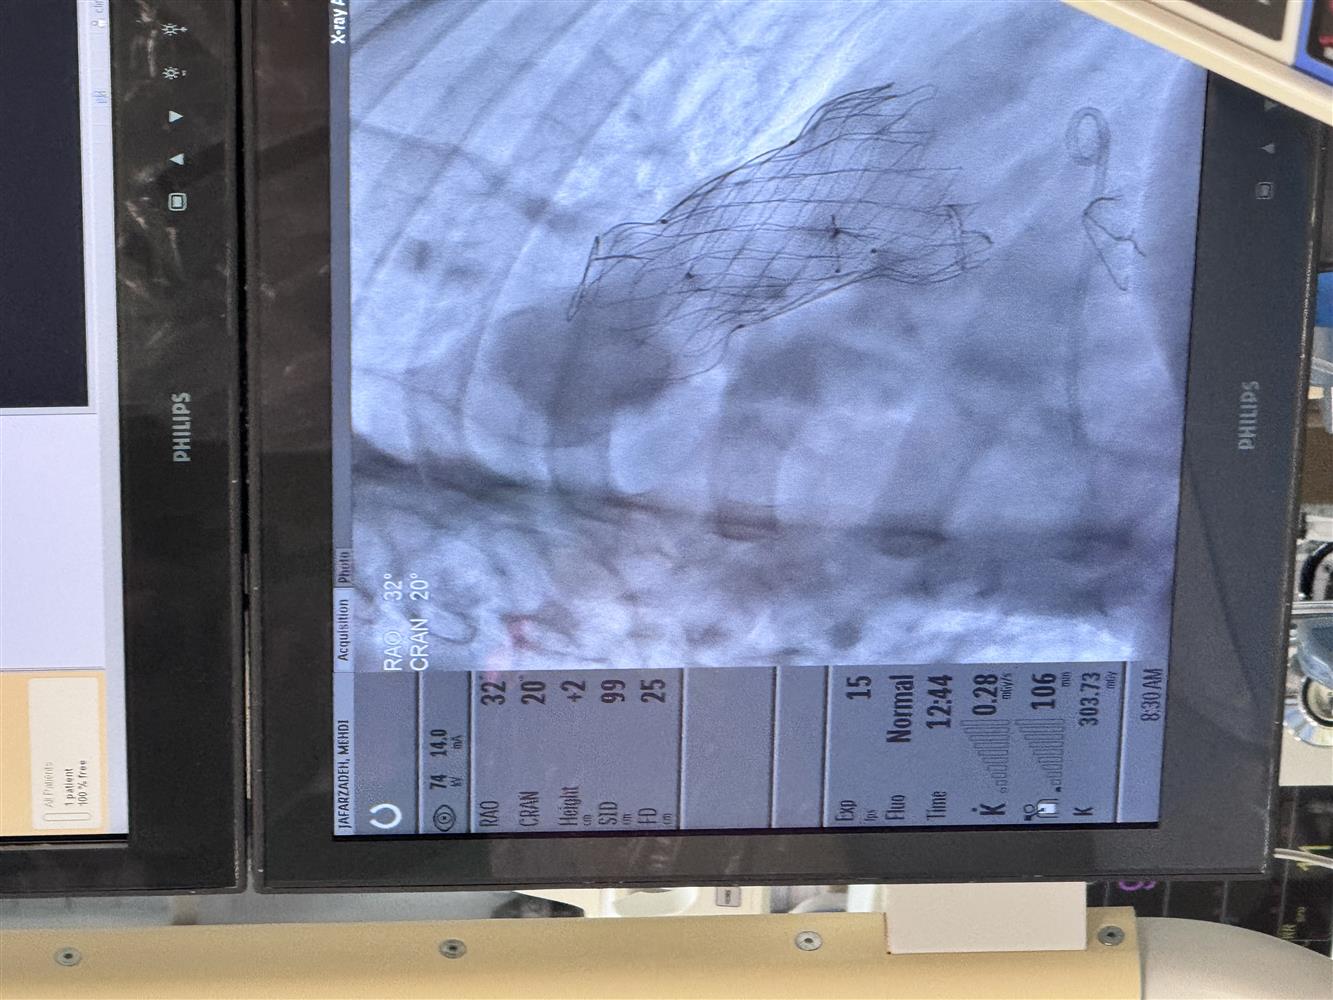

این پروسیجر پیشرفته در سرویس فوق تخصصی قلب و عروق بیمارستان فوق تخصصی مدائن زیر نظر مستقیم دکتر علی اکبر زینالو فوق تخصص قلب کودکان برای بیمار با سابقه مادرزادی تترالوژی فالوت قلب جهت جاگذاری دریچه مصنوعی فلزی از طریق اینترونشن با نتیجه بسیار خوب انجام شد.

این اقدام که در سطح کشور بسیار کم انجام میشود گامی مهم در ارتقاء خدمات درمانی بیماران قلب و عروق به شمار می رود.